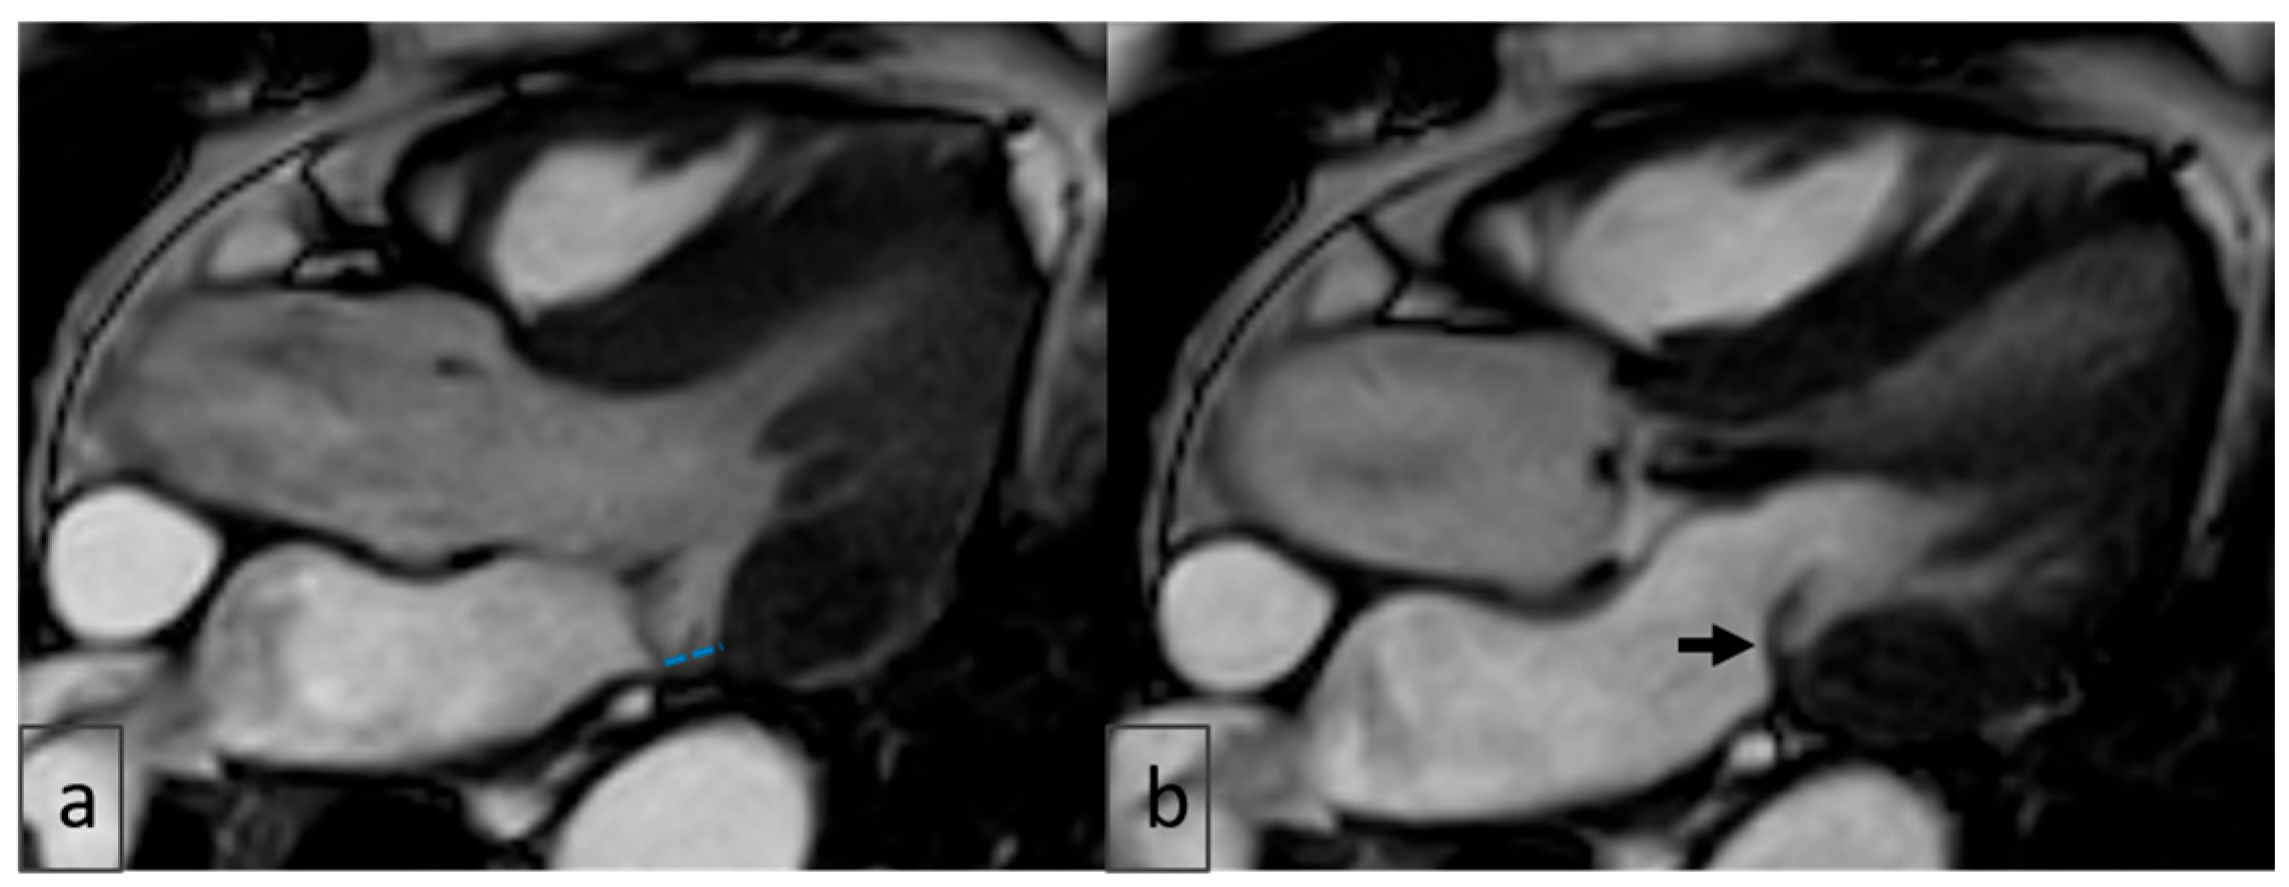

2.4. Image Analysis

3.6. Cardiac MRI Findings in MAD